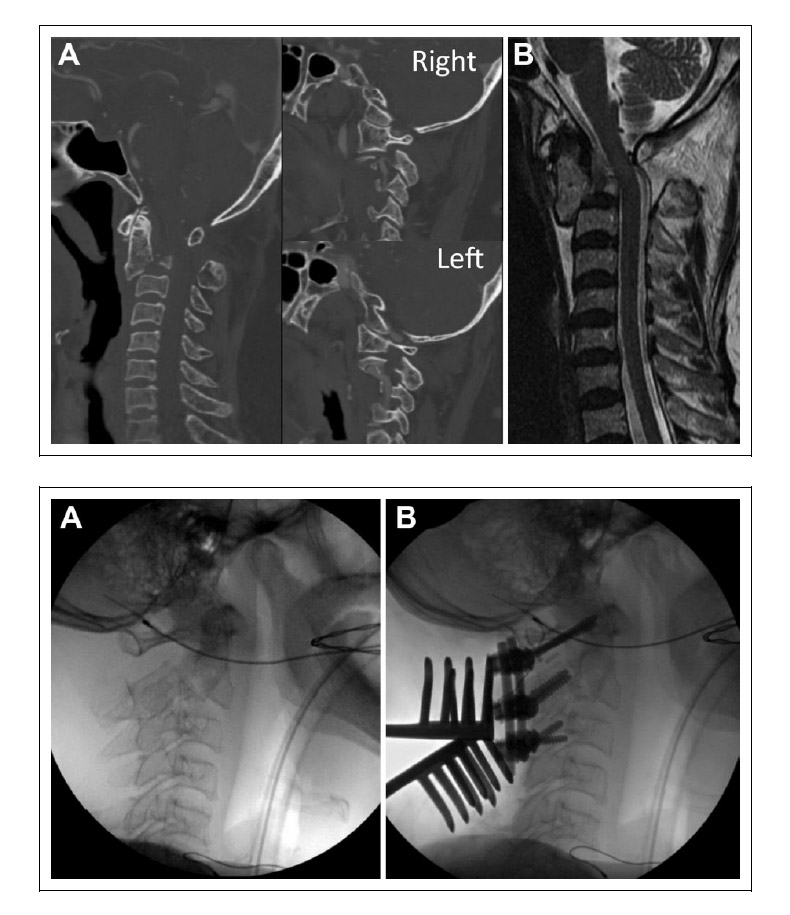

Bello et al 3 presents an example of an MIONM alert in their article on multimodal intraoperative neurophysiological monitoring during positioning of patient prior to cervical spine surgery (shown below).

Charalampidis A et al, 4 in their article on the use of intraoperative neurophysiological monitoring in spine surgery, presents an interesting case showing a good clinical outcome achieved using MIONM.